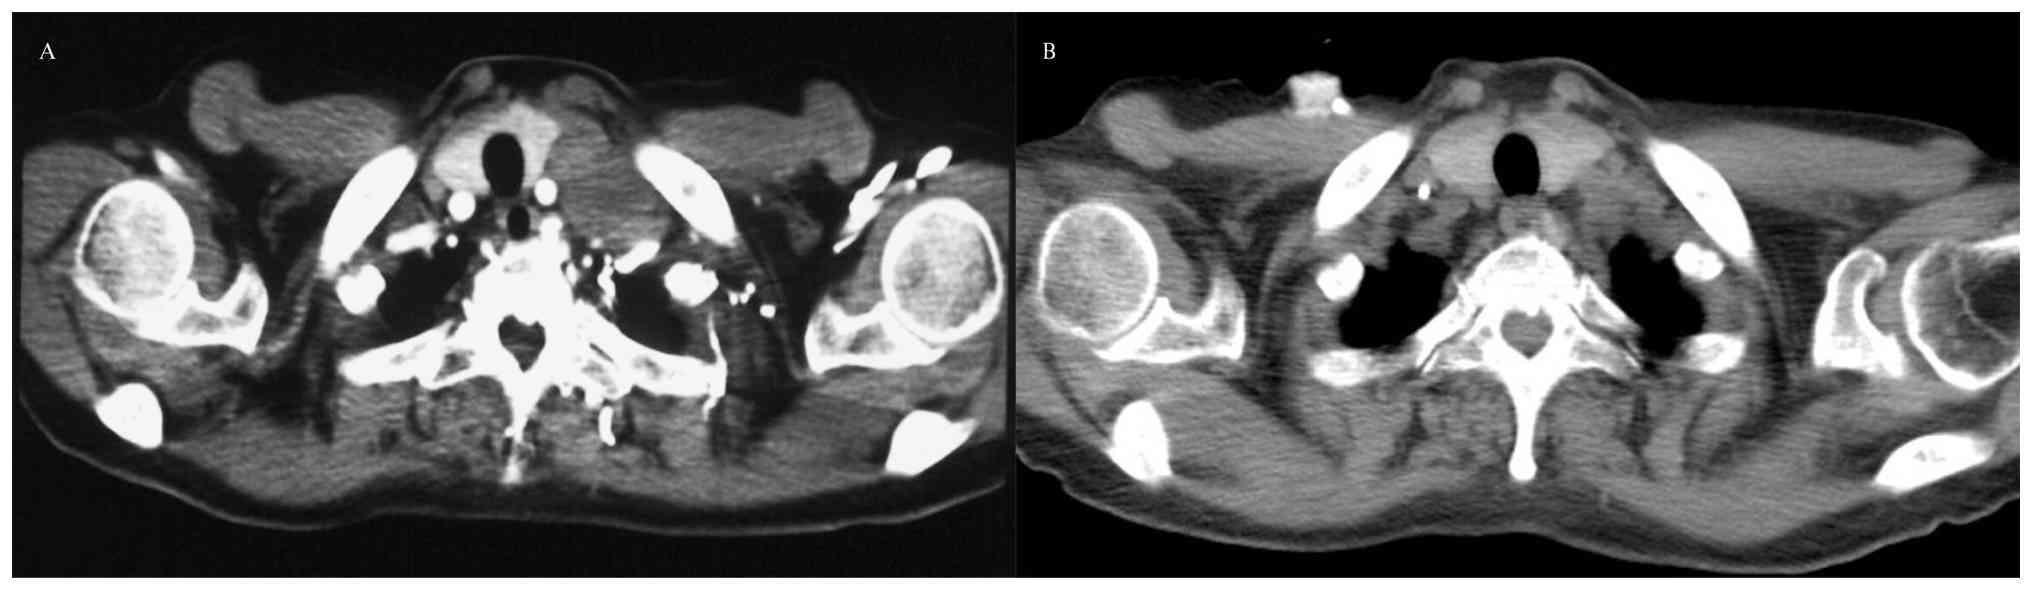

A 63-year-old Chinese woman presented to an external hospital with a self-detected left supraclavicular mass in May 2020. The patient had no history of smoking, autoimmune disease or familial cancer, and denied any history of psychiatric or neurological disorders. Neurological examination revealed no abnormalities. Computed tomography revealed a 6.9×5.0-cm mass at the left hilum, with multiple enlarged lymph nodes in the mediastinum and supraclavicular regions (Fig. 2A).

Computed tomography images of the left

hilum mass (A) before and (B) after chemotherapy combined with

immunotherapy.

Figure 2.

Computed tomography images of the left hilum mass (A) before and (B) after chemotherapy combined with immunotherapy.

In June 2020, the patient was diagnosed with extensive-stage SCLC based on the results of biopsy of the left supraclavicular lymph node (hematoxylin and eosin staining and immunohistochemical staining performed using standard procedures; obtained from the pathology report; images are not available). Magnetic resonance imaging (MRI) before medical treatment showed no abnormal findings in the brain (Fig. 3). Subsequently, 2 days later, the patient was administered one 21-day cycle of chemotherapy with a combination of etoposide [100 mg/m2 intravenously (iv), days 1–3] and cisplatin (area under the curve 5 mg per ml/min iv, day 1). After three cycles of treatment, computed tomography depicted partial regression of the primary tumor and metastatic lymph nodes (Fig. 2B). In August 2020 (2 weeks after the second dose of atezolizumab), the patient developed self-reported confusion and short-term memory loss. Further physical examination revealed impairments in temporal and spatial orientation as well as poor calculation ability.